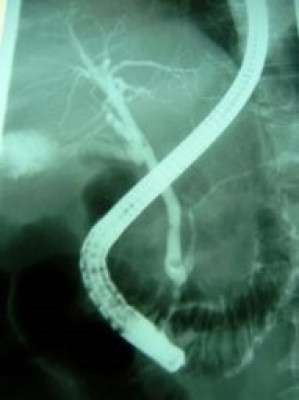

Coledocolitiasis pancreatitis biliar

Envíado por Dr. Carlos Miguel Zavaleta Consuegra